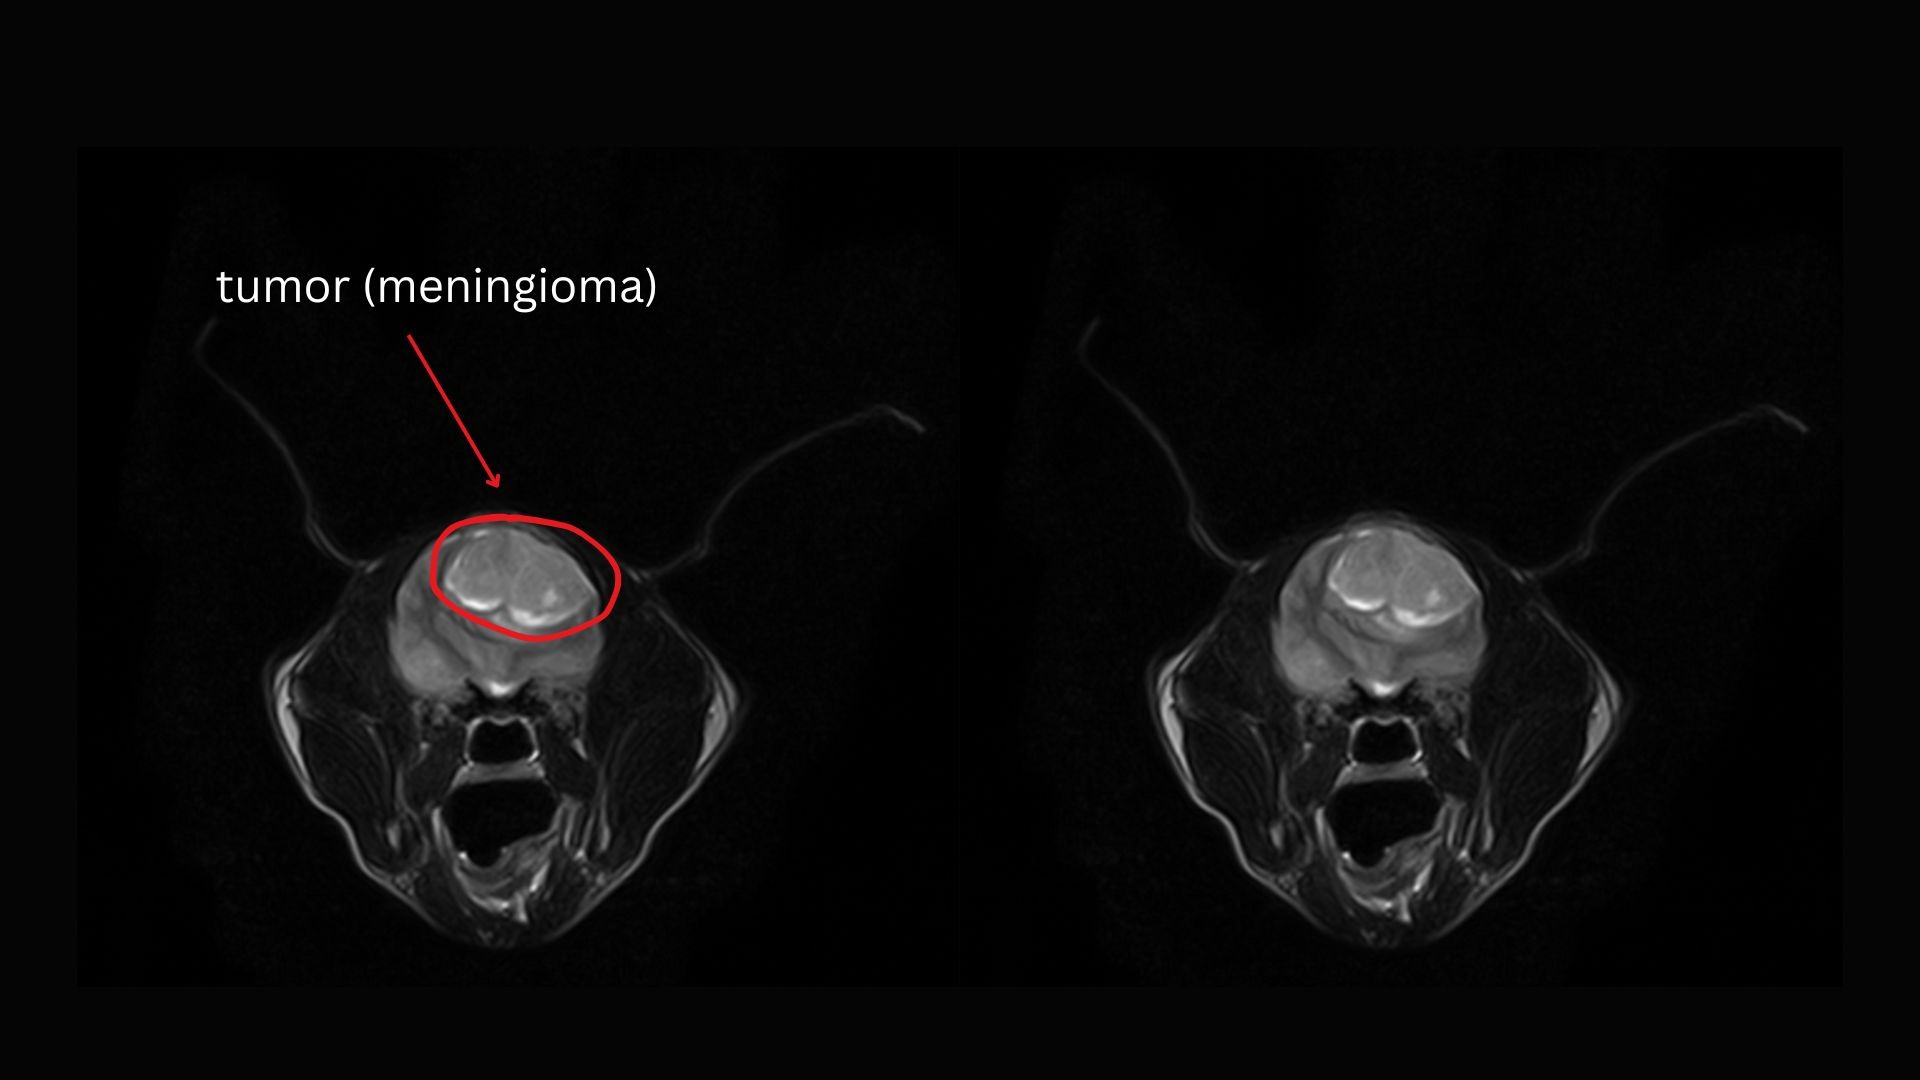

On October 30, we took Wendy to Remedy, where she underwent anesthesia and an MRI scan, which revealed a large meningioma that was putting immense pressure on her brain. Dr. Mona Qahwash, the neurologist, expressed her concern that, without surgery, "Wendy could pass away at any moment", as the tumor could begin to interfere with vital reflexes, including her ability to breathe.

Wendy's MRI's: